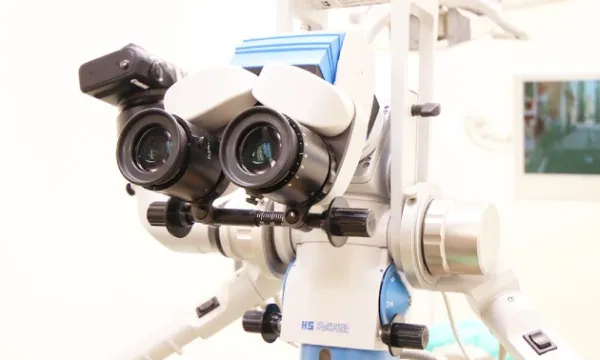

また、湿度が多い口の中でしっかり接着力をきかせるには厳格な防湿処理が必要だということです。さらに、歯の隣り合わせたところにまで虫歯が進んだ場合、しっかり段差なく詰めるにはかなりの技術が必要であるということです。 マイクロスコープを用いて仕上げれば、全く段差なく仕上げることが可能ですが、非常に時間を要し、確認するのも容易ではありません。手軽で短時間で仕上がり、それなりの審美性を得られる利点がありますが、術後問題になる症例も決して少なくない方法なのです。

炎症が神経にまで及ぶと、一般的には痛みが起こり神経に炎症が波及し根の治療になることが多いです。しかし、神経に炎症が波及しても、神経すべての部位で細菌が広がり、炎症が起こり神経が死んでしまうわけではありません。 神経にも炎症に対する抵抗力があり、それ以下の炎症ならば生き抜くことも十分考えられます。つまり、回復が望めない部位のみ神経を取り除き、それ以下の神経は回復を期待して残すという考え方です。 そこで、当院ではマイクロスコープを駆使し、神経の切断面と出血の状態を観察することによって神経の状態を観察し、生き残ると思われる部分から先の神経を残すことを行っています。

マイクロスコープとMTAを用いたい治療法

当院では、特殊なケースの根管充填で用いてきたMTAを応用しています。MTAを用いた場合は、水酸化カルシウムを用いた場合と同じように、切断面に歯の堅い壁を作り、さらに神経の器は細くならない特徴があります。 残念ながら、MTAを用いた治療法は保険適応ではありませんが、後戻りのできない「取り除く」という治療を回避できる可能性があります。マイクロスコープ導入で、利用機会が増えたMTA。よりダメージが少なく、歯に優しい方法であると考えています。 神経を残せるかどうかの瀬戸際の歯にとって、ラストチャンスの治療法として提案しております。

不幸にして神経をとらなければならなくなった場合は、神経が回復不可能、つまり死ぬ方向に進んでしまった場合に行います。まず、健全な歯の部分はなるべく削らず、更に根の治療が効率的に出来るように形成します。すると神経の上の部分がまず露出します。この部分は髄室といいます。 この部分の神経をしっかりとれるように角の部分(髄角)までしっかり形を作ります。その後、その下にある根の部分の神経の入り口(根管口)を探します。歯の種類に種類によって大まかな数は決まっていますが実際にはそれより多いことが多いので顕微鏡を使って慎重に探索し、取り残しのない様にします。 根管口が見つかったら神経を根の先まで探索し神経を除去します。神経はまっすぐなことはないので、途中で曲がった道に追従できずに進まなくなったり、また誤って別の道を作ったりしないように慎重に行います。